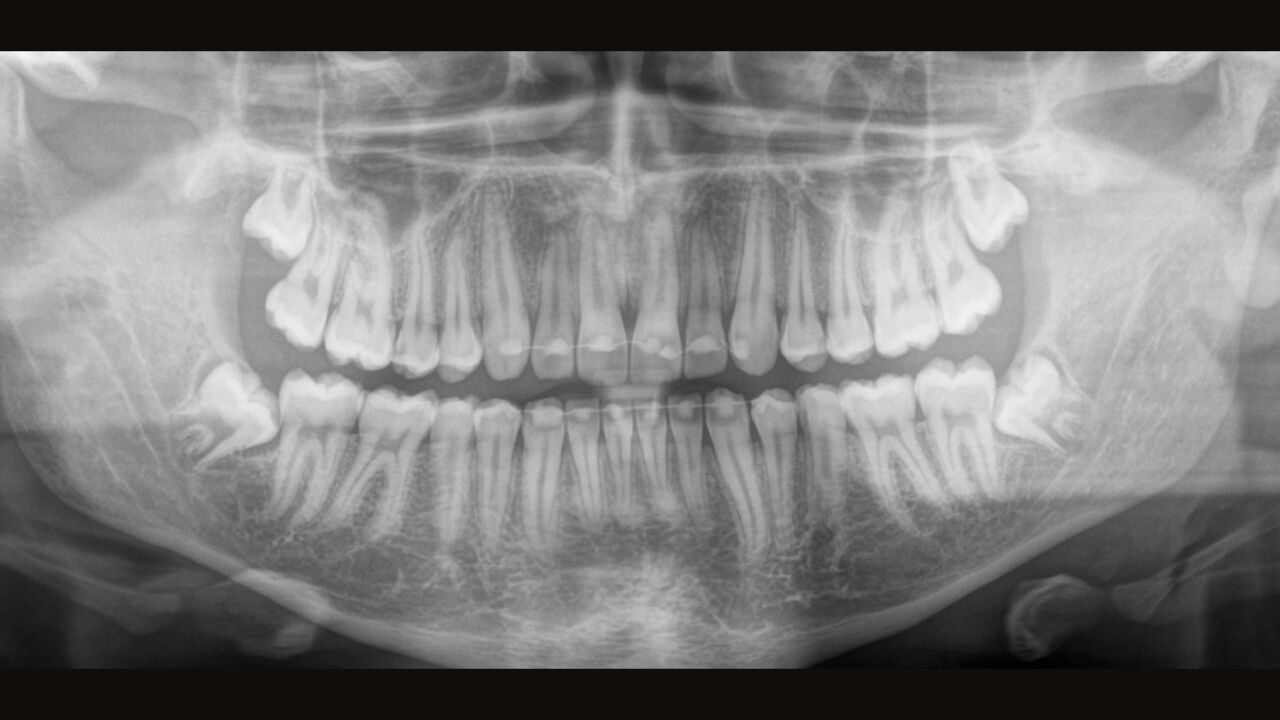

El equipo de radiología 2D/3D de alta calidad con una amplia gama de servicios para cada clínica. Ya sea como un dispositivo puramente 2D o como un módulo 3D, el Orthophos S es un socio confiable y está optimizado para las tareas diarias. Su sensor CsI Plus con función de autofoco garantiza imágenes claras, incluso en casos anatómicamente difíciles. El posicionamiento automático del paciente junto con el bloque de mordida oclusal patentado permite un posicionamiento del paciente fácil y que ahorra tiempo. Para su uso en ortodoncia, la Orthophos S también está disponible con un brazo cefalométrico opcional. Y como para Dentsply Sirona es importante estar preparado para el futuro, el brazo cefalométrico se puede reacondicionar en cualquier momento.

Para la mayoría de las clínicas, se utiliza un equipo de radiología con dos objetivos principales en mente: capturar la mejor imagen posible para respaldar un diagnóstico preciso y exacto, y garantizar que el paciente se sienta cómodo durante el proceso. El Orthophos S ofrece soluciones únicas y patentadas para apoyar ambos objetivos con:

El enfoque correcto es crucial para excelentes radiografías panorámicas. Con la función de autofoco, usted recibirá automáticamente una imagen con la mejor nitidez posible en foco. Los dispositivos de radiología de Dentsply Sirona toman varios miles de imágenes individuales en un ciclo e identifican automáticamente las áreas donde la mandíbula está posicionada de manera óptima. Luego, sin ningún paso manual adicional, estas imágenes se muestran en una nítida imagen final.